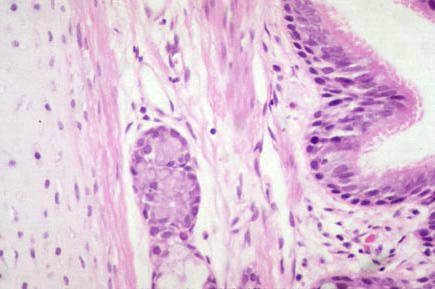

High power of fig. 6, with pseodostratified respiratory epithelium at top and cartilage at bottom.